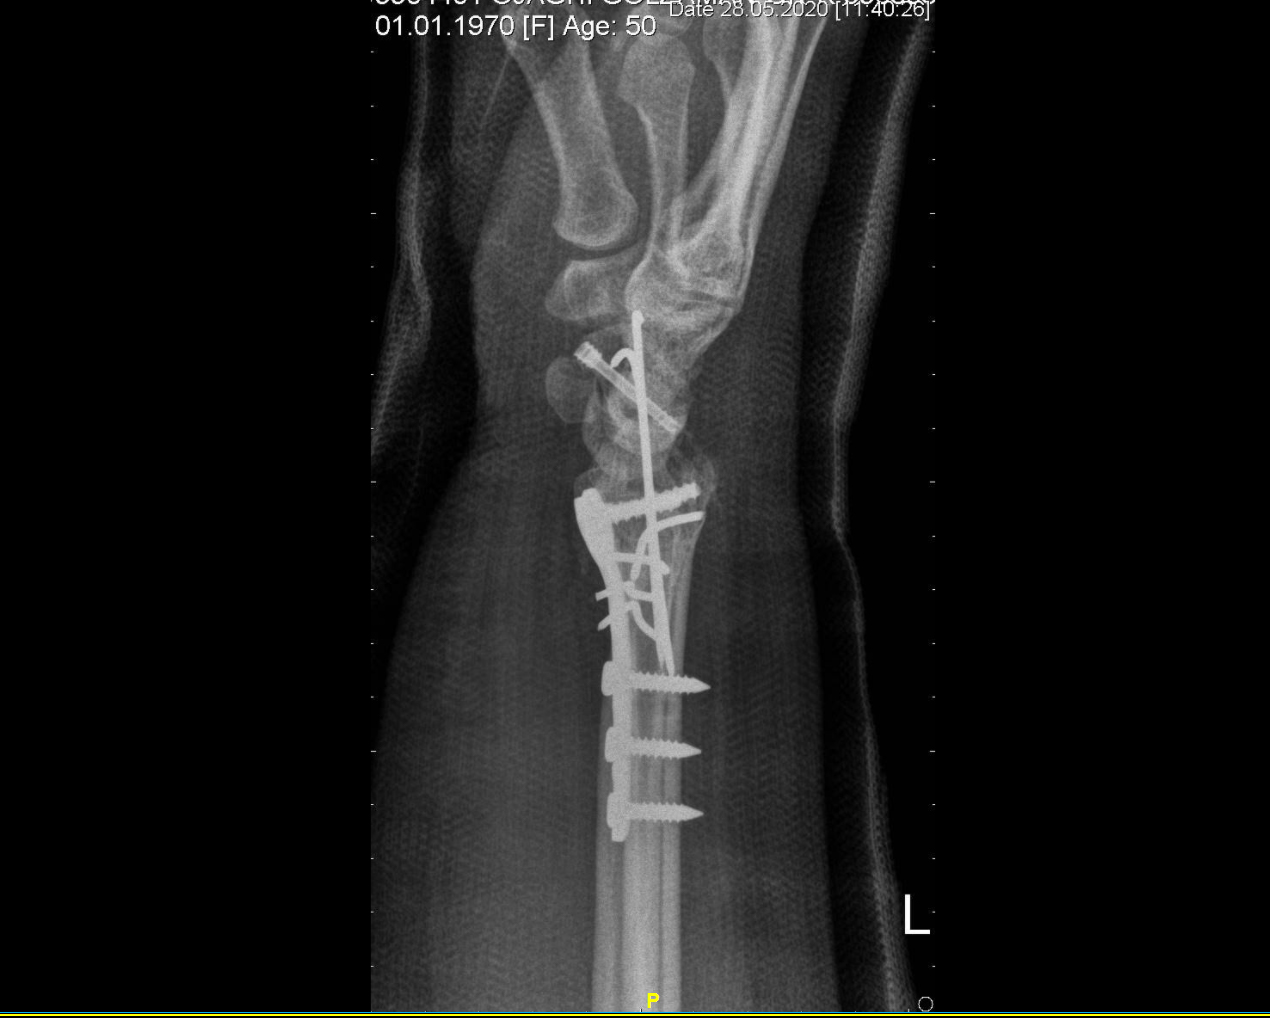

شکستگی خرد شده دیستال رادیوس و اسکافویید

خانم ۴۹ ساله که به دلیل واژگونی موتور چهارچرخ در ساحل انزلی، دچار شکستگی خرد شده مچ دست شده است. شکستگی دیستال رادیوس و اسکافویید و دررفتگی مفصل رادیواولنار به ترتیب فیکس شدند.